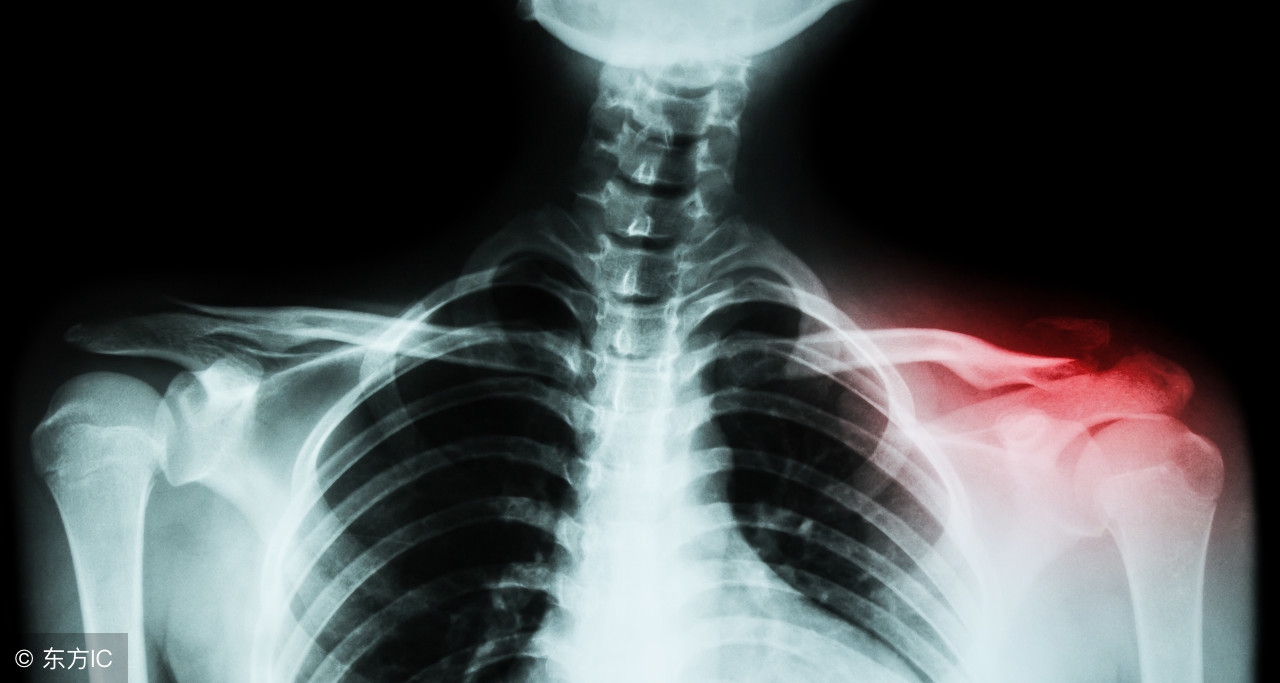

这张成年人的胸片让我们容易发现锁骨骨折的部位(红色区域)